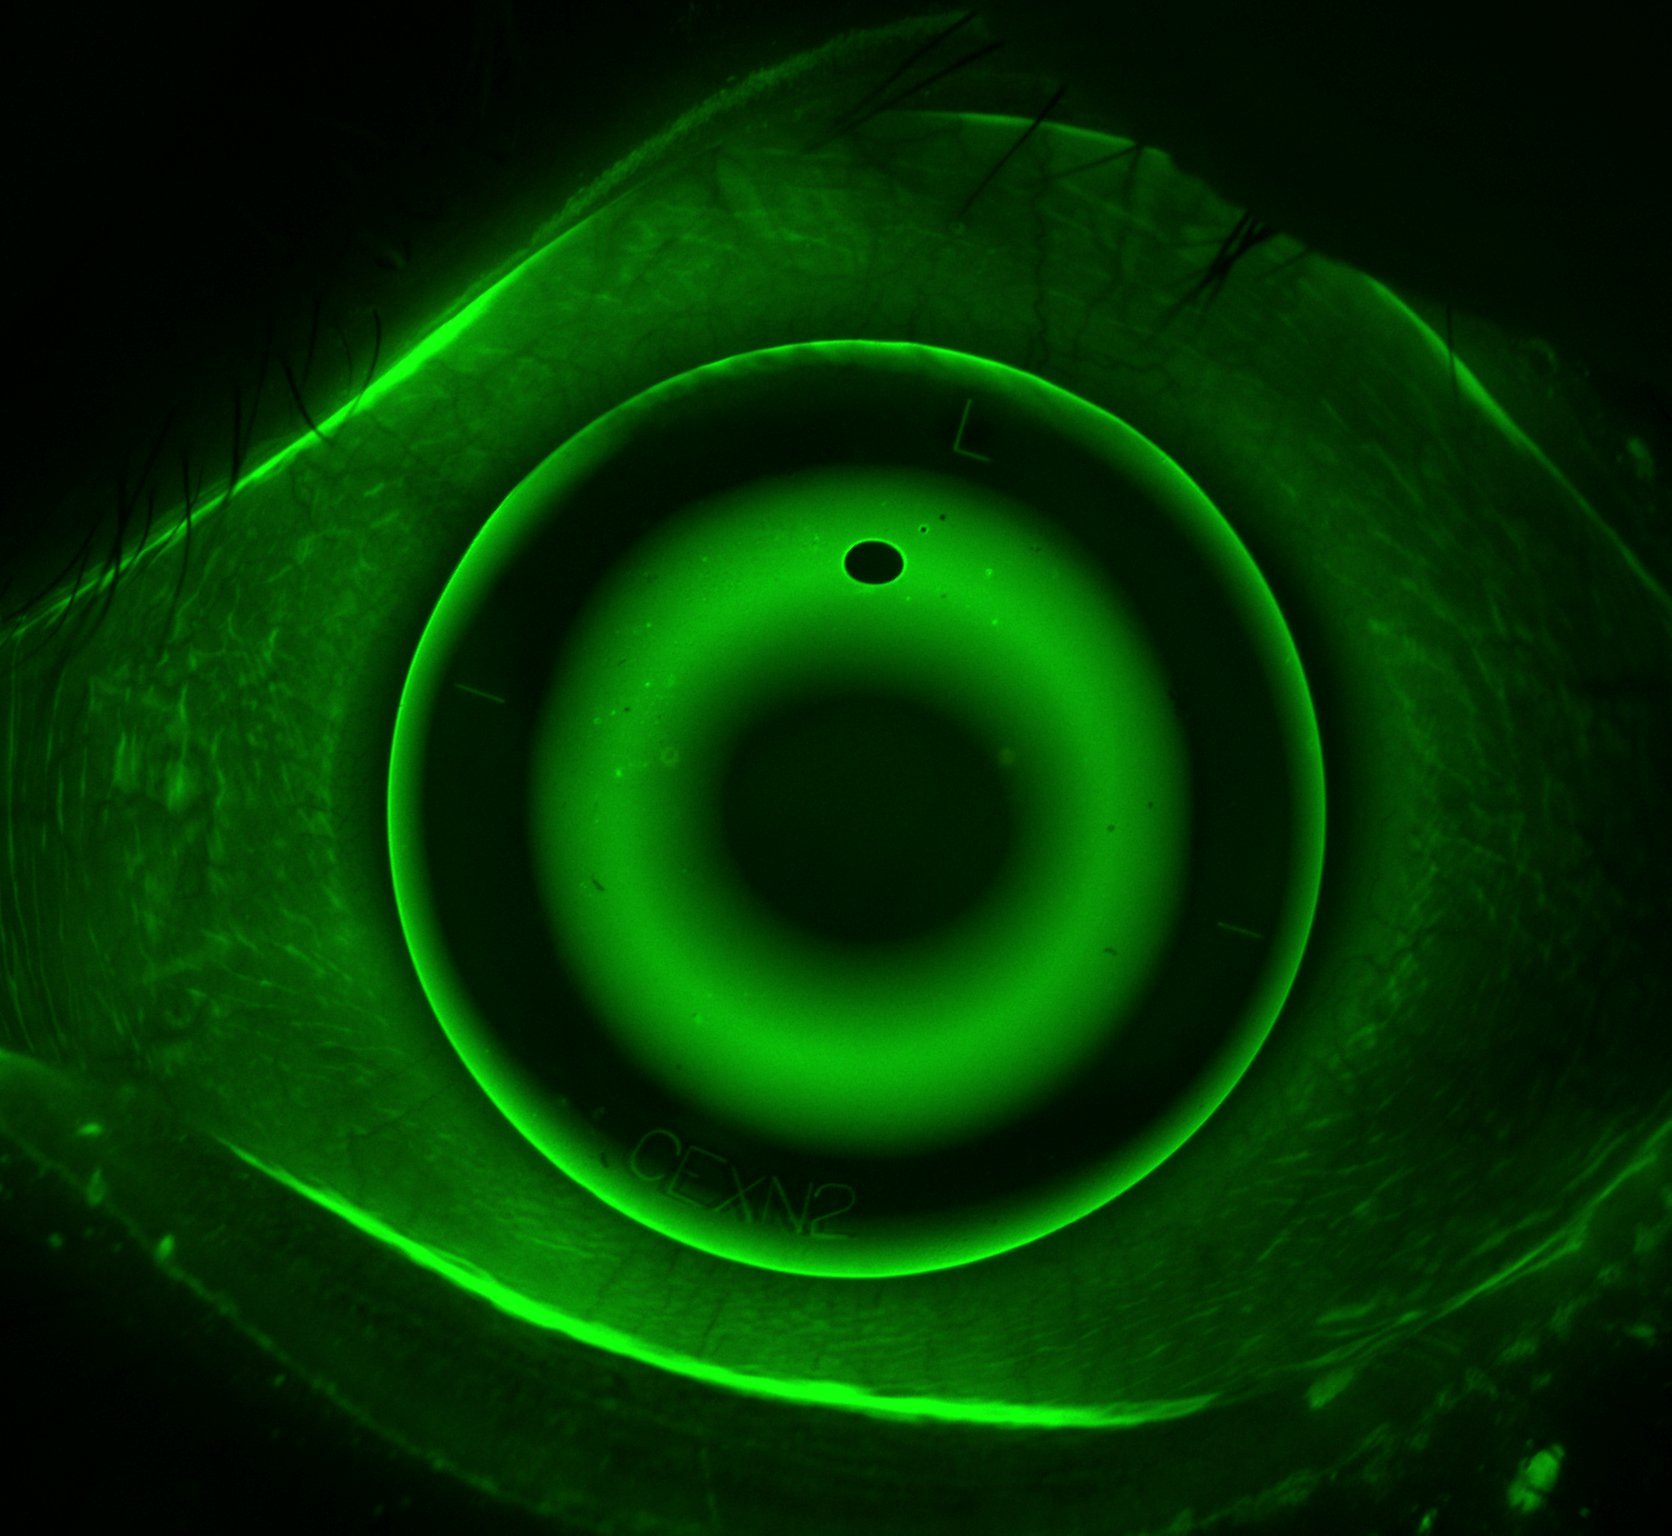

Purely eye related causes of headache include ocular surface disease, inflammation within the eye, raised pressure within the eye, eye strain from uncorrected refractive error, eye alignment problems and excessive focussing.